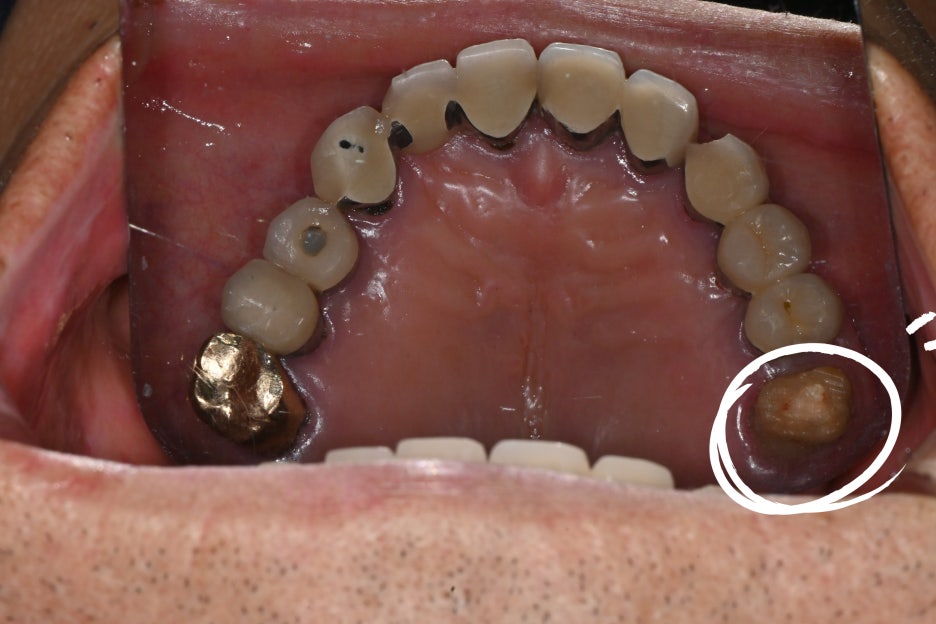

The patient’s molar had decay progressing beneath the restoration,

damaging the tooth up to near the root,

so root canal treatment was essential.

The patient had significant periodontitis and a buildup of tartar,

so we first performed panoramic imaging and tartar removal.